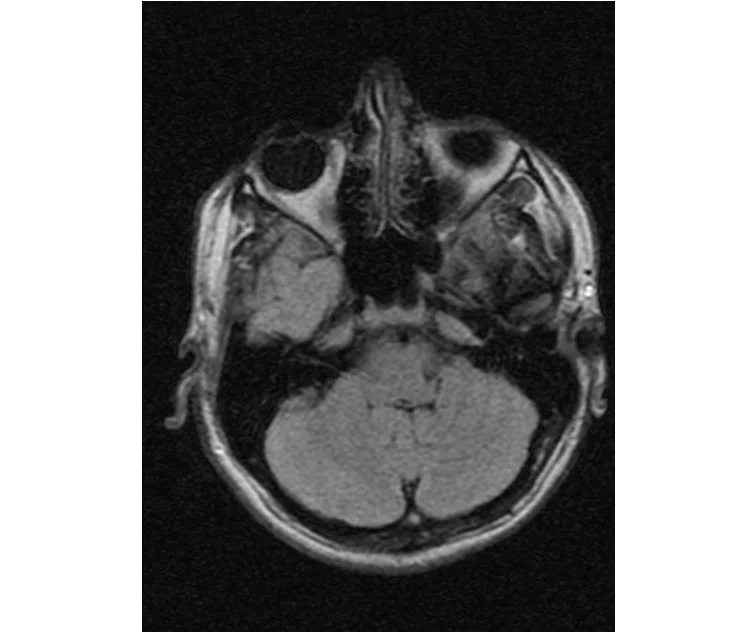

глянте на снимки томографии плиз

делал в обласной на siemense.В заключении выданом мне через 15мин.после мрт (легкая дегидрация)

Меня смутил факт выдачи заключения через 10мин(наверно они у них зарание напечатаные)я не медик.достаточно мимолётного взгляда на снимки?А вы видете на них гидроцефалию? Я лиш спросил куда идти с результатами томографии?и не хотел никого роздражать.

Я попросил взглянуть на снимки и сказать видна.ли на них гидроцефалия?или куда обратится за консультацией по этому вопросу?В мрт снимках наверно розбирается любой нервопатолог(я так предположил)

Я уже говорил, что независимо от того, есть на МРТ гидроцефалия или нет, лечиться тебе нужно только в том случае, если есть какие-либо проявления болезни, иначе на все эти анализы можешь забить... Но давай все-таки разберемся с томограммой.

Ты разместл здесь несколько миниатюр и хочешь, чтобы врач по ним создал полноценное объемное изображение в натуральную величину, а потом осмотрел его со всех сторон и дал заключение? Но ведь это невозможно. Это просто насмешка над врачом, это издевательство над здравым смыслом. Принеси Букеру уменьшенный в 50 раз снимок зуба и спроси у него, в каком состоянии там корневые каналы. Или давай я дам тебе скрин со спутниковой карты города и попрошу тебя описать, какого цвета и какой модели запечатленная со спутника машина, какой у нее гос.номер, сколько в ней пассажиров, сколько из них мужчин и сколько женщин...